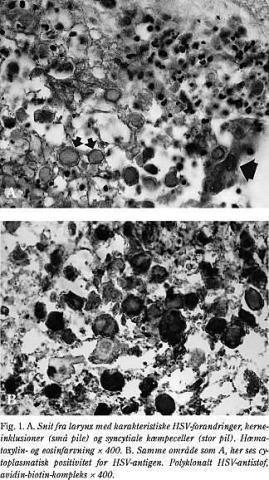

Ved sektionen sås blødninger i huden og i de indre organer samt gangræn af fingre og tæer i overensstemmelse med den klinisk påviste DIC. I lungerne fandtes svære forandringer i overensstemmelse med sent stadium af adult respiratory distress syndrome . I de øvre luftveje var der udbredt pseudomembranøs inflammation lokaliseret til epiglottis, larynx og pharynx. En mikroskopi viste klassiske herpesforandringer (Fig. 1A og Fig. 1B), og ved en supplerende immunhistokemisk undersøgelse påviste man HSV. Der var ikke tegn på generaliseret infektion i leveren og nyrerne.